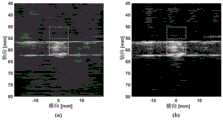

Fig. 4 shows the results obtained by using the conventional passive ultrasound imaging method (a) and the high-resolution passive ultrasound imaging method (b) proposed by the present invention.

referring to fig. 4, wherein (a) and (b) are the imaging results of cavitation activity in the process of irradiating phase-change nano-droplets by focused ultrasound obtained by the traditional passive ultrasound imaging method (without using double apodization cross-correlation and amplitude coherence coefficient) and the high-resolution passive ultrasound imaging method proposed by the present invention, respectively, and the dynamic range is 50 dB. It can be seen that the imaging artifacts are significantly reduced in fig. 4(b) compared to fig. 4(a), indicating that the spatial characterization of the cavitation activity is more accurate. Through calculation, the transverse half-width at half maximum of the result shown in fig. 4(a) is 1.61mm, the axial half-width at half maximum is 20.72mm, the transverse half-width at half maximum of the result shown in fig. 4(b) is 0.94mm, the axial half-width at half maximum is 6.49mm, and the transverse half-width and the axial half-width of the result shown in fig. 4(b) are both lower than the result shown in fig. 4(a), which indicates that the high-resolution passive ultrasonic imaging method provided by the invention effectively improves the spatial resolution of imaging.